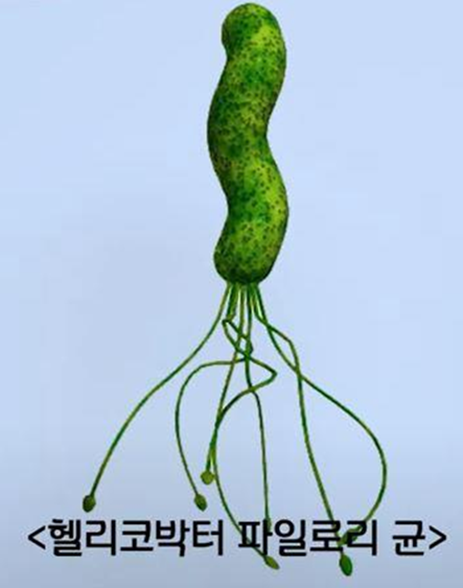

Хеликобактер пилори – бактерия, обитающая в желудке и вызывающая повышенное образование желудочного сока. При хроническом присутствии хеликобактер пилори вызывает разрушение клеток и выработку токсинов, что в свою очередь повышает риск развития рака желудка.

Лечение хеликобактер пилори требуется в следующих двух случаях:

1. Язва ЖКТ+ хеликобактер пилори 2. Наличие хеликобактер пилори после удаления рака желудка на начальной стадии |

[Изображение 1] Хеликобактер пилори

Если результат анализа на хеликобактер пилори положительный, следует проконсуль-тироваться со специалистом.